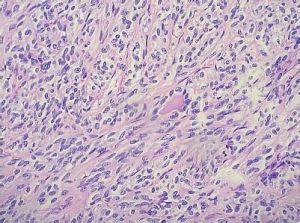

梭形細胞腫瘤主要是以梭形細胞為主,可發生在任何器官或組織,形態學表現可以是癌也可以是瘤。如發生在上皮組織(如梭形細胞癌、梭形細胞鱗癌),也可以發生在間葉組織(如梭形細胞肉瘤,梭形細胞間質肉瘤),形態表現複雜,多類似肉瘤,或伴有形似肉瘤的間質成份,免疫表型既可表現為癌,也可表現為肉瘤,或表現為癌肉瘤結構等的一類腫瘤。該病變較難直接檢查,需多方面的檢測如免疫組織化學標記等。

以梭形細胞為主的腫瘤類型很多,除肉瘤外還有一些癌和惡性黑色素瘤:當細胞分化程度低時,進行組織類型診斷常較困難。在觀察切片進行鑑別診斷時,可以從以下幾方面入手,逐層剖析。 (1)首先從腫瘤發生的部位和病人年齡出發,初步分析肉瘤、癌或惡性黑色素瘤何者可能性大。低分化的軟組織肉瘤和惡性外周神經腫瘤多發生於人體較深部的組織,肌肉、腹膜後、盆腔、縱隔和內臟器官,與組織表面被覆的皮膚或黏膜上皮關係不密切、低分化的梭形細胞癌多見於被覆鱗狀上皮或移行上皮的器官組織如鼻咽、食管、膀胱,腫瘤與上皮關係密切,有潰瘍形成。此外,肺、甲狀腺等器官內也可見梭形細胞癌。惡性黑色素瘤則多見於皮膚及外胚層來源的黏膜。對兒童和20歲以下的青少年多考慮肉瘤,成年人則肉瘤和癌都有可能。

(3)梭形細胞的形態和排列方式可以在一定程度上提供腫瘤組織類型的線索。例如纖維肉瘤細胞的胞質通常不如肌源性細胞豐富,胞質寬度一般不超過核的寬度,細胞邊界也不如後者的清楚;而肌源性腫瘤細胞可呈長梭形或帶狀.胞質內可見縱行的原纖維,橫紋肌肉瘤的胞質嗜伊紅染色較強。纖維肉瘤的梭形細胞束多呈人字形排列;車輻狀結構多見於惡性纖維組織細胞瘤,其他梭形細胞性肉瘤中亦可見,但較少且不甚典型。核柵狀排列在惡性神經鞘膜瘤和中度分化的平滑肌肉瘤中雖不如相應的良性腫瘤中明顯,但仍有時可見。